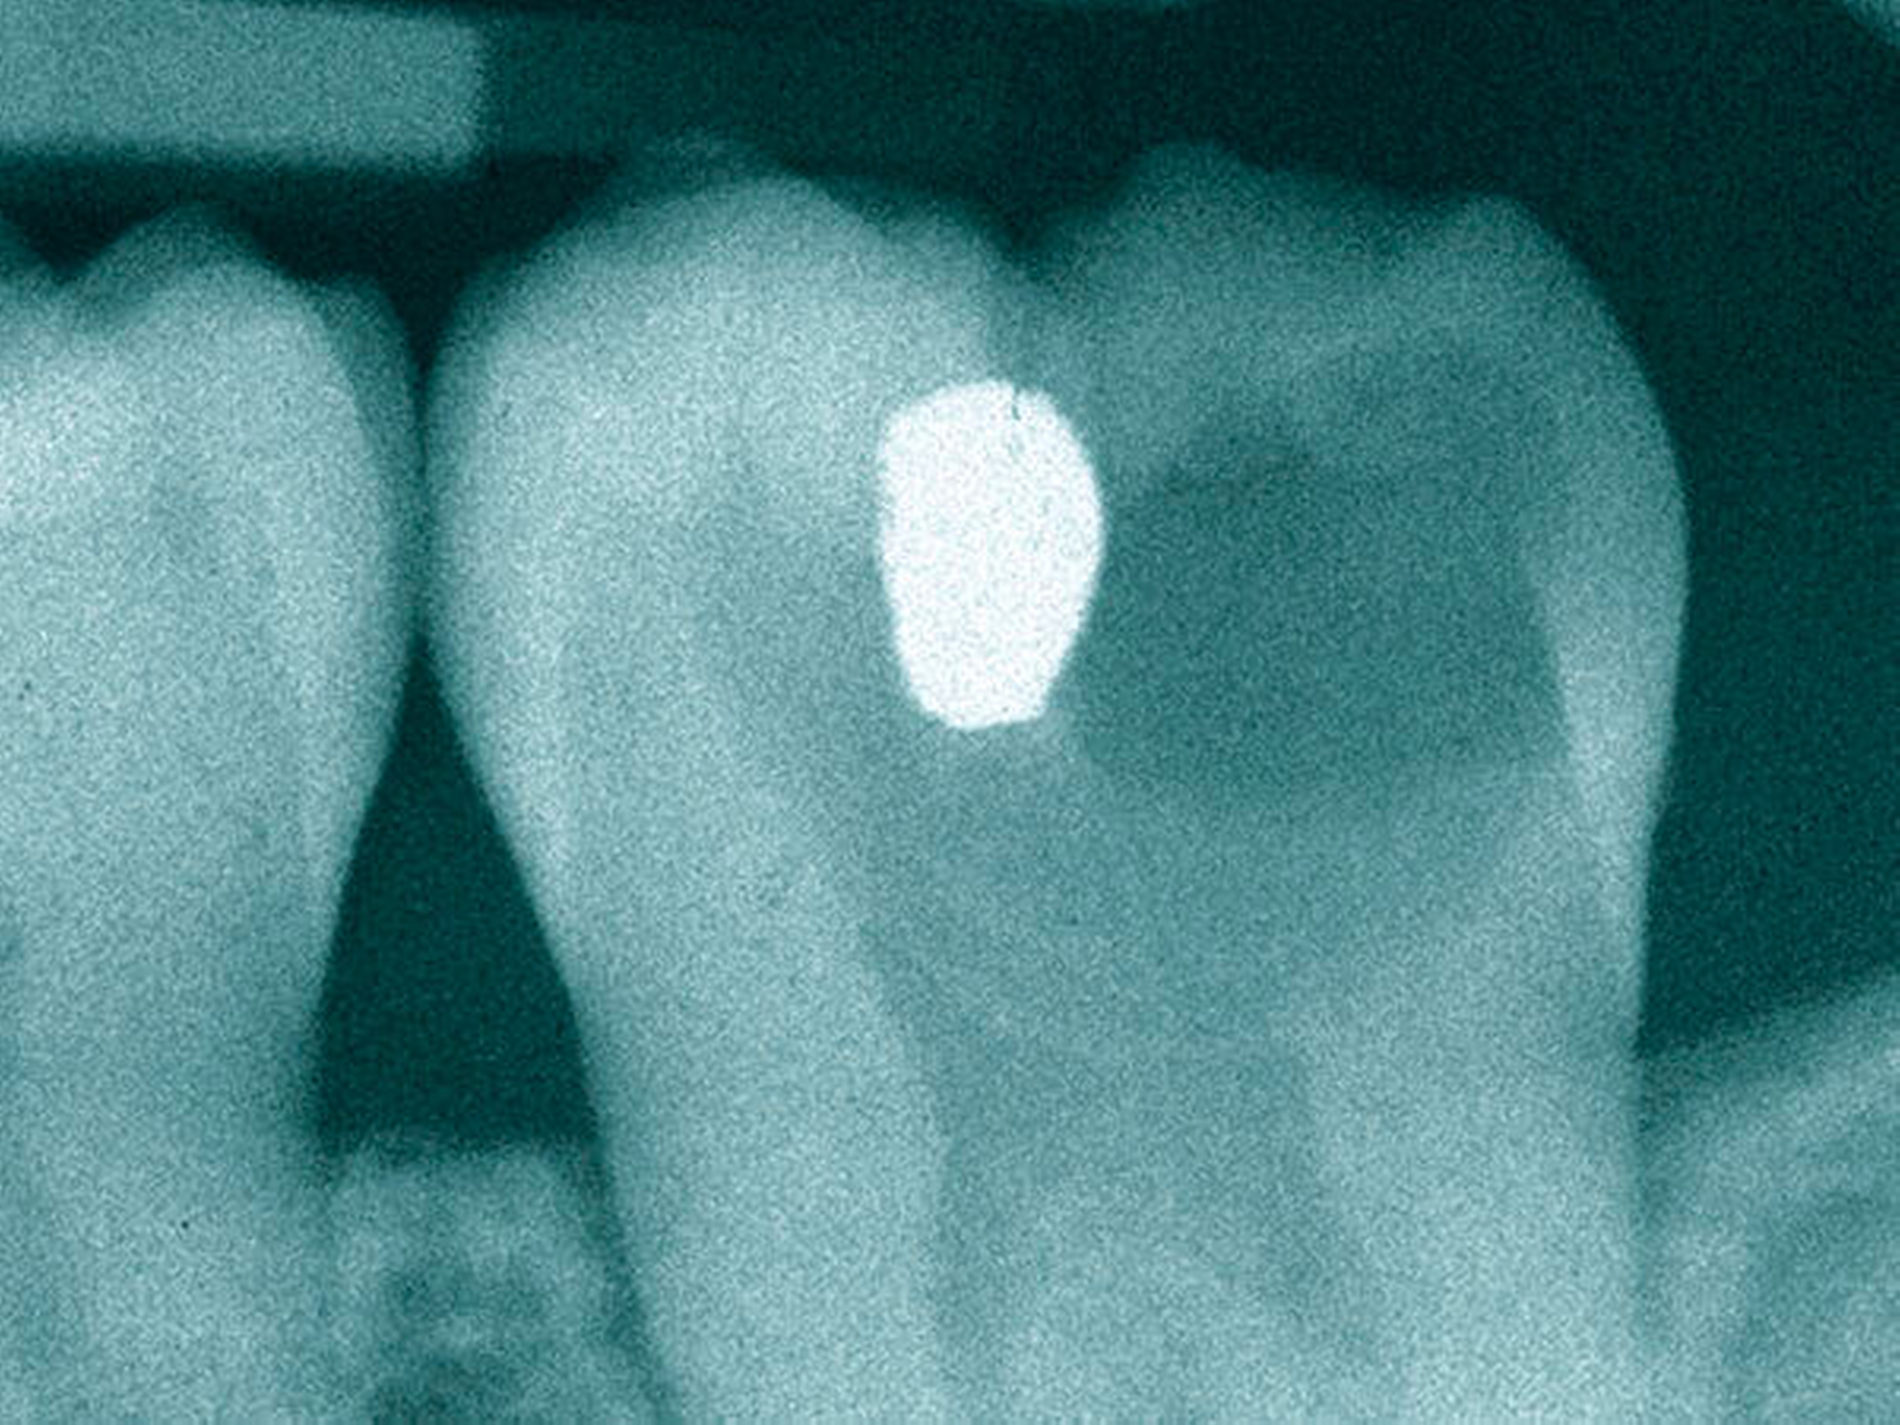

Die Experten empfehlen möglichst non- oder minimal-invasive Therapiestrategien, außer bei aktiver Karies mit einer nicht reinigungsfähigen Kavitation. Das Gremium unterschied die okklusale von der Approximalkaries und bezog die Ausdehnung der Karies auf dem Röntgenbild als Entscheidungskriterium mit ein.

Prof. Dr. Lars Bjørndal aus Kopenhagen warb für ein vertieftes Verständnis der Pathologie der Karies. Je nach Tiefe der Läsion auf dem Röntgenbild stehen dem Behandler unterschiedliche Strategien zur Verfügung. Doch trotz der immer umfangreicheren Evidenz aufgrund vieler Studien zum Thema „selektive Kariesexkavaton“ befolgten viele Zahnärzte die Empfehlungen nicht. 50 Prozent der Zahnärzte vernachlässigten laut einem aktuellen Review evidenzbasierte Strategien zur Kariesentfernung.

Das schrittweise Exkavieren der Karies

Entfernung von kariös erweichtem Dentin von peripher nach zentral. Ein Rest an weichem, kariös verändertem Dentin wird pulpanah belassen, um eine Eröffnung zu vermeiden (= selektives Exkavieren). Dieses kariöse Restdentin wird mit Calciumhydroxid abgedeckt. Im Anschluss wird für etwa zwölf Monate eine Glasionomerzement-Füllung gelegt.

Nach sechs bis zwölf Monaten wird das restliche kariöse und inzwischen erhärtete Dentin vollständig entfernt. In aller Regel sollte sich nach dieser Zeit eine Schicht von Tertiärdentin an der Stelle gebildet haben. Dadurch kann in vielen Fällen erneut eine Pulpaeröffnung vermieden werden. Im Anschluss wird eine definitive Füllung gelegt.

Bedingungen für dieses Vorgehen:

1. Der Patient ist weitestgehend schmerzfrei, insbesondere existiert kein persistierender und kein Nachtschmerz.

2. Der Zahn ist vital und erhaltungswürdig.

3. Es gibt keine apikale Aufhellung an dem betroffenen Zahn auf dem Röntgenbild.

Quelle: Lars Bjørndal